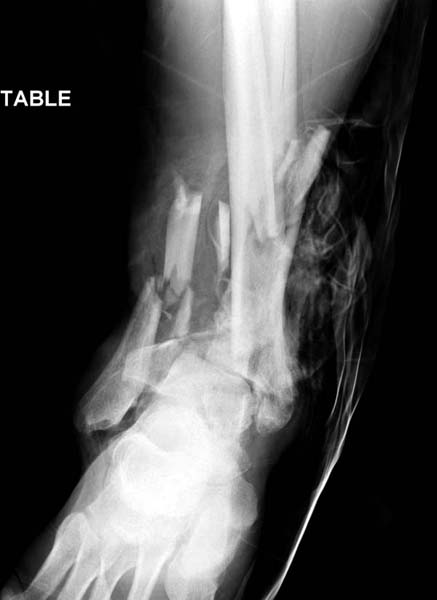

Современную тактику лечения переломов пилона описали коллеги, а мне остается подтвердить клинически. В многоэтапном лечении главное - это предупреждение сокращения мягких тканей, от которого зависит судьба конечности. Дистракция любым наружным фиксатором, и по готовности мягких тканей - премежуточная или окончательная фиксация.

В нашем случае, травма в результате коллапса крыши. Открытый перелом. Ургентные Irrigation and Debridment, дистракция наружным фиксатором. В госпиталях первого уровня редко бывает изолированная травма, и на другой стороне повреждение стопы с переломом навикулярной кости. После обработки раны - вакуум и двухсторонние наружные фиксаторы.

Вначале нет смысла заказывает КТ, только дистракция организует на свое место свободных фрагментов. По топографии отломком преоперационный план, а готовность мягкой ткани подтвердит появившиеся морщины на поверхности кожи, “Wrinkle Sign”.